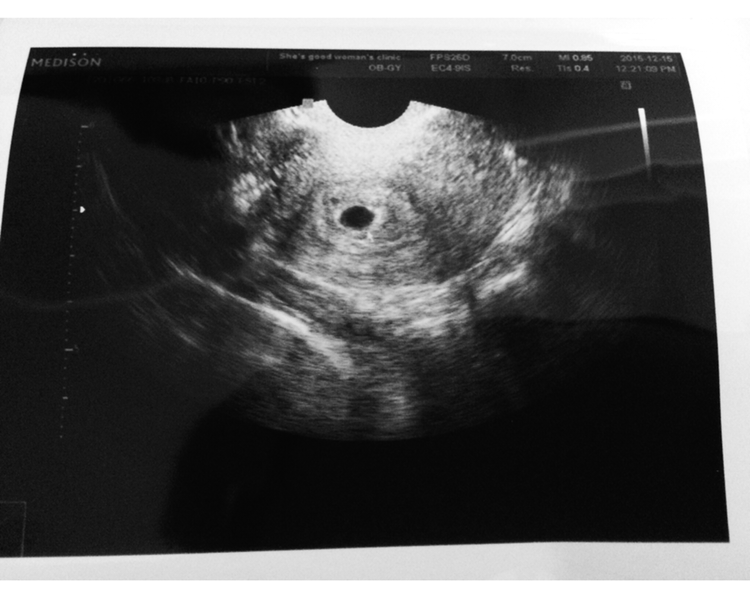

검사는 나를 당황스럽게 하기도 했다. TV에서 본 것 처럼 편안하게 침대에 누워 배 초음파를 하는 것이 아닌 의자에 앉아 질초음파를 검사 하는 것이었다. 아이를 낳아본 엄마들은 다 알겠지만 임신 초기엔 아기집이 잘 보이지 않아서 질초음파로 검사하는데 사실 난 이 검사가 뭔가 수치스러우면서도 너무 아파서 눈물까지 흘렸었다.

하지만 이내 들려오는 의사선생님의 말씀.

'아기집이 잘 자리 잡고 있네요. 4주정도 됐어요. 축하드립니다.'

아직 아무것도 보이지 않는 내 뱃속의 작은 땅콩만 한 아기집. 난 집으로 돌아와서도 아이의 초음파 사진을 보며 혼자 얼마나 웃었는지 모른다. 하지만 그와 함께 엄습해오는 두려움들. 나는 사진을 보면서 혼잣말로 계속 되뇌이고 있었다.